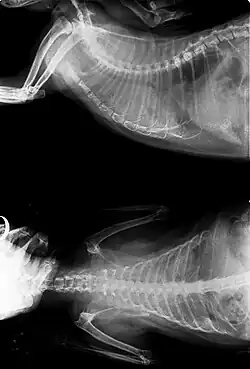

Cancer can be detected at an early stage by observing certain signs and symptoms. Common diagnostic methods include physical examination, x-rays, ultrasounds, cytology, blood tests, urine tests, and nuclear scans. Depending on the type of cancer and its level of progress, surgery, radiation, chemotherapy, or immunotherapy may be used to treat the cancer. Although research into causes and treatment of feline cancers has been slow, there have been advances in radiation therapy, as well as newer and improved chemotherapy procedures.[2]

- X-rays may or may not make use of contrast techniques to help visualize the gastrointestinal tract. They are commonly used to identify tumours of the lung, gastrointestinal tract and bladder.